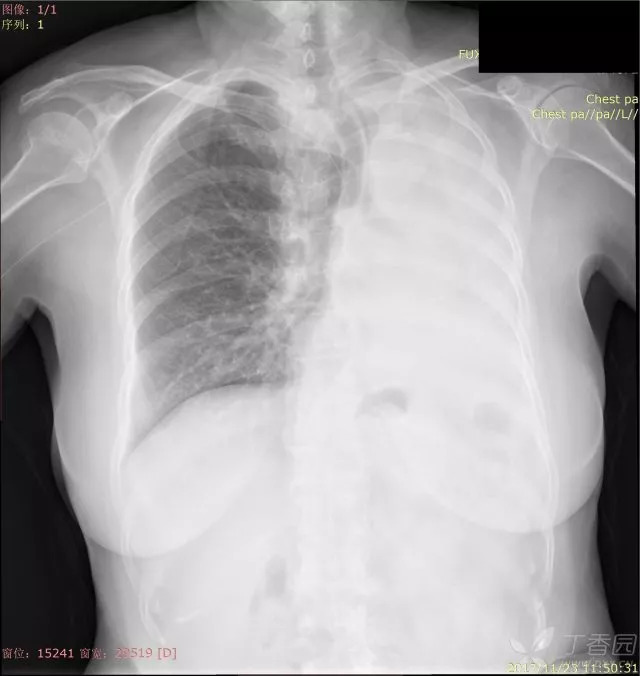

之前我们分享了秒懂胸片!扒一扒胸片的基础知识(可点击查看),那这一次就老生常谈,先发一波病例走起,病例很简单,都是白肺,各位来诊断吧。备选一共有:上叶肺不张、全肺不张、胸腔积液、大叶性肺炎

1.大叶性肺炎

2.胸腔积液

3.全叶肺不张

4.上叶肺不张